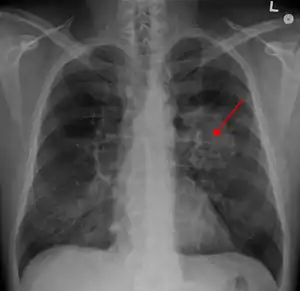

| A chest X-ray showing a tumor in the lung (marked by arrow) | |

A person suspected of having lung cancer will have imaging tests done to evaluate the presence, extent, and location of tumors. First, many primary care providers perform a chest X-ray to look for a mass inside the lung.[8] The X-ray may reveal an obvious mass, the widening of the mediastinum (suggestive of spread to lymph nodes there), atelectasis (lung collapse), consolidation (pneumonia), or pleural effusion;[9] however, some lung tumors are not visible by X-ray.[5] Next, many undergo computed tomography (CT) scanning, which can reveal the sizes and locations of tumors.[8][10]

Lung cancer can often appear as a solitary pulmonary nodule on a chest radiograph or CT scan. In lung cancer screening studies as many as 30% of those screened have a lung nodule, the majority of which turn out to be benign.[15] Besides lung cancer many other diseases can also give this appearance, including hamartomas, and infectious granulomas caused by tuberculosis, histoplasmosis, or coccidioidomycosis.[16]